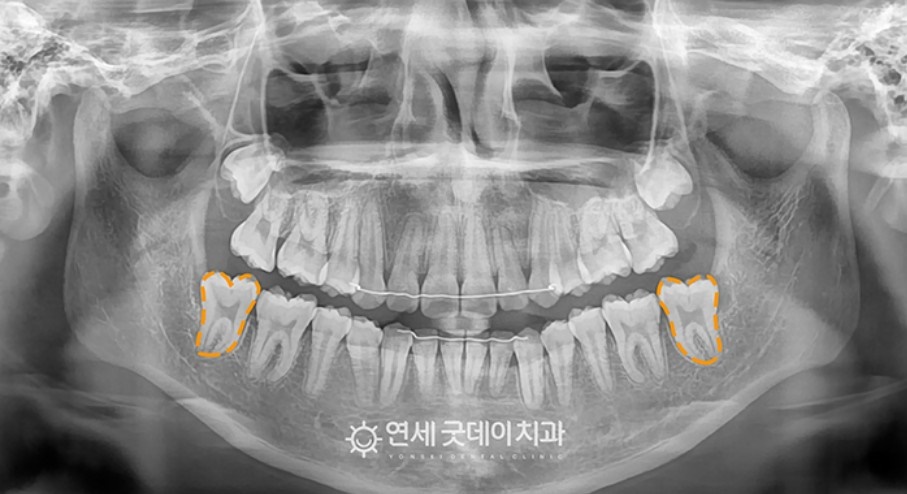

이제 구강외과 전문의 협진을 통해 견인교정하는 과정입니다.

우선 잇몸은 열고 사랑니는 발치한 뒤, 바로 세워야 하는 치아에 나사를 심고 장치를 붙여서 철사로 연결하는 구강외과 수술을 시작했습니다.

위 사진을 살피면 점차 치아가 서기 시작하는 것을 볼 수 있고, 마지막에는 교정치료를 적용해 자연스러운 치열을 얻을 수 있었습니다.

난이도가 높은 케이스였지만 간단한 국소마취 하에 30분 가량의 수술 시간으로 깔끔하게 치료해 드렸습니다. 결과적으로 틀어져 있던 위 덧니는 짧은 시간 내에 가지런해지고, 웃을 때도 치아 배열이 고르게 바로 잡혔습니다.

전과 후를 비교함으로서 삐뚤어져 있던 덧니와 치아중심선이 바로잡힌 모습이 더 잘 보입니다.

매복치아 부분도 예쁘게 해결되었습니다.

엑스레이상으로 그 차이를 뚜렷하게 볼 수 있으며 치료 이후로도 교합이나 기능적으로도 잘 쓰고 있는 것을 확인할 수 있었습니다.